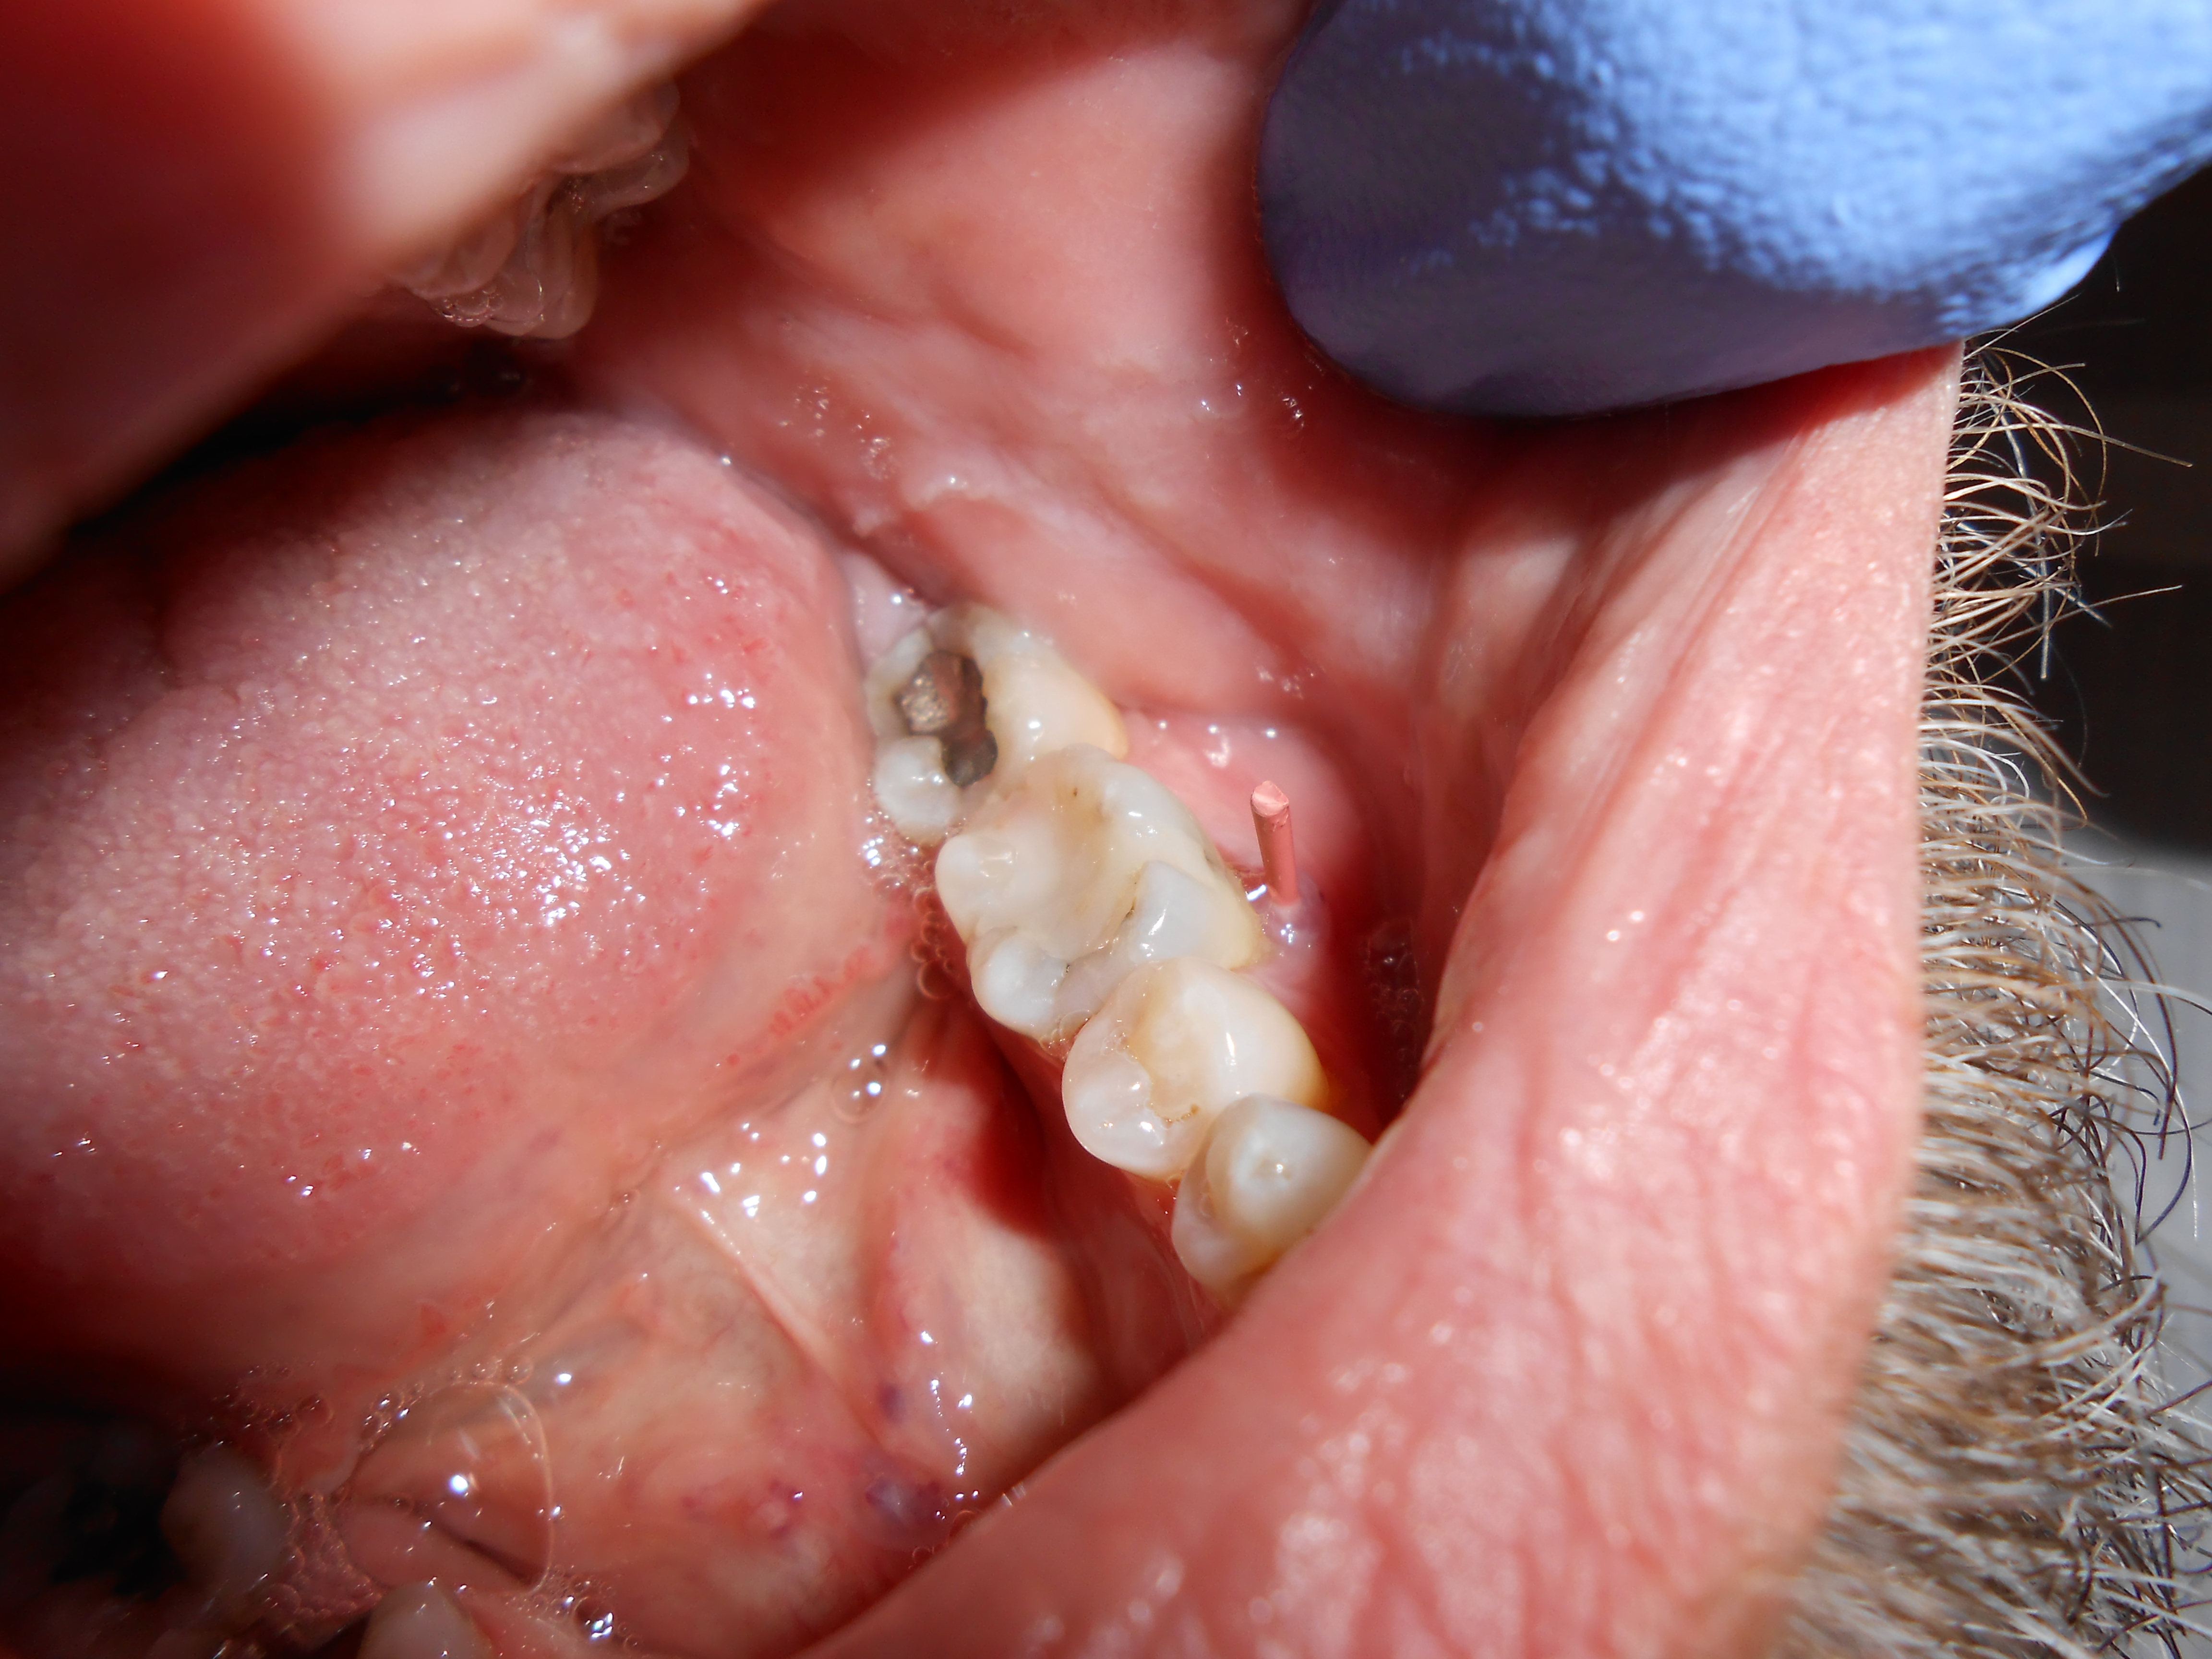

Fig 4. A pulp polyp is a clinical example of an asymptomatic irreversible pulpitis diagnosis.

Figure 4

Asymptomatic irreversible pulpitis is a vital pulp that is incapable of healing, and endodontic treatment is consequently indicated. Although asymptomatic irreversible pulpitis is actually a histologic diagnosis to determine the inflammatory extent of the pulp, clinical examples of this diagnosis include a pulp polyp and internal resorption (Figure 4).